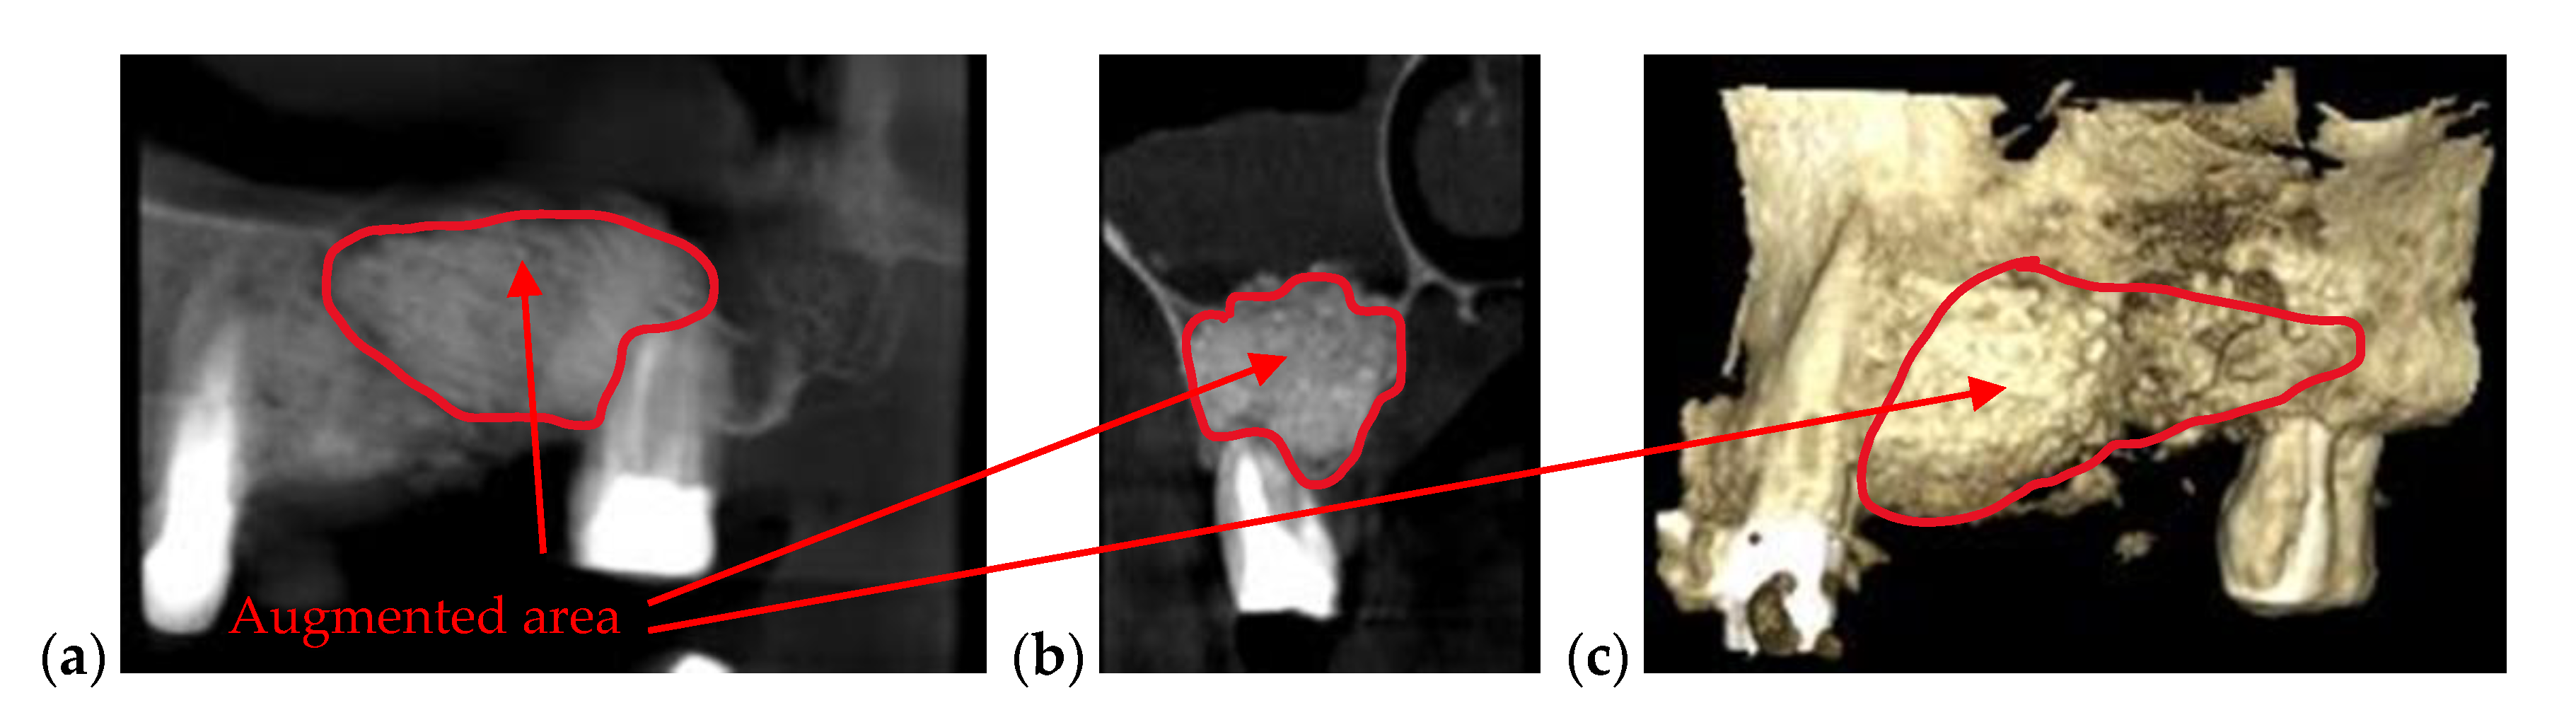

| Bone issues assessment | Accurate investigations of bone density and quantity assessment on 3D CBCT images (see the example in Figure 3) | Cannot penetrate through the bone more than 1 to 2 mm |